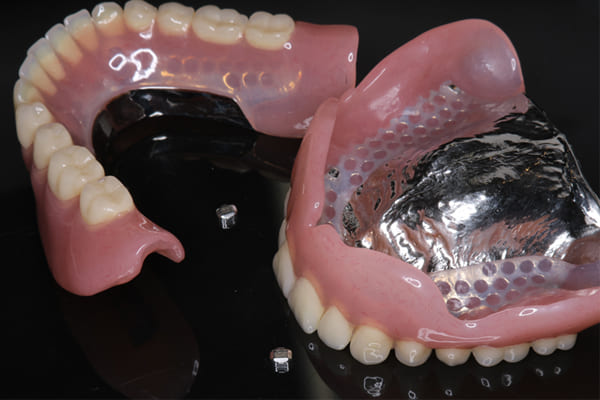

- 治療

- 下顎精密金属床部分入れ歯

入れ歯が沈み込むことを防止するストッパーがない入れ歯を装着されていたため、お食事により入れ歯が沈み込みお痛みがでている状態でした。

作製した入れ歯は、お食事の際に入れ歯の沈み込みを予防するため、適切なストッパーを付与することで、入れ歯は沈み込まなくなり、お痛みは消失しました。

右下のバネの位置は後ろに、左下のバネは見えづらい形態のバネを用いる設計とすることで笑った際にバネが見えないようになり、気にされることはなくなられました。

裏側の見えない部分は金属を用いることで、お食事の際の入れ歯の動き、沈み込みを抑えお痛みがでづらく、入れ歯の動きが抑制されることで、長期的に残りの歯に負担のかかりにくい設計としました。